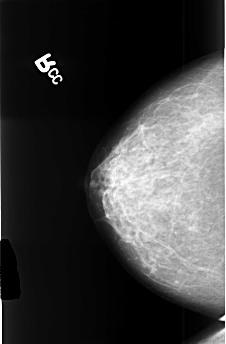

B_3477_1.RIGHT_CC

RIGHT_CC LINES 4464 PIXELS_PER_LINE 2936 BITS_PER_PIXEL 12 RESOLUTION 50 NON_OVERLAY

RIGHT_MLO LINES 4496 PIXELS_PER_LINE 2928 BITS_PER_PIXEL 12 RESOLUTION 50 NON_OVERLAY